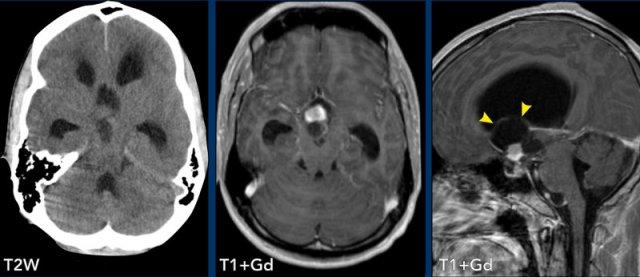

Các hình ảnh này của một phụ nữ 63 tuổi mắc bệnh von Hippel-Lindau.

Hãy quan sát kỹ. Dấu hiệu nào khó nhận thấy?

Hình ảnh

Có một nang lớn với một nốt nhỏ ngấm thuốc ở bán cầu tiểu não phải.

Thành nang không ngấm thuốc.

Lưu ý nốt u nằm ở phía màng mềm (mũi tên).

Có thêm hai nốt nhỏ ngấm thuốc ở mặt sau của tiểu não.

Đa u hầu như luôn liên quan đến bệnh von Hippel-Lindau.